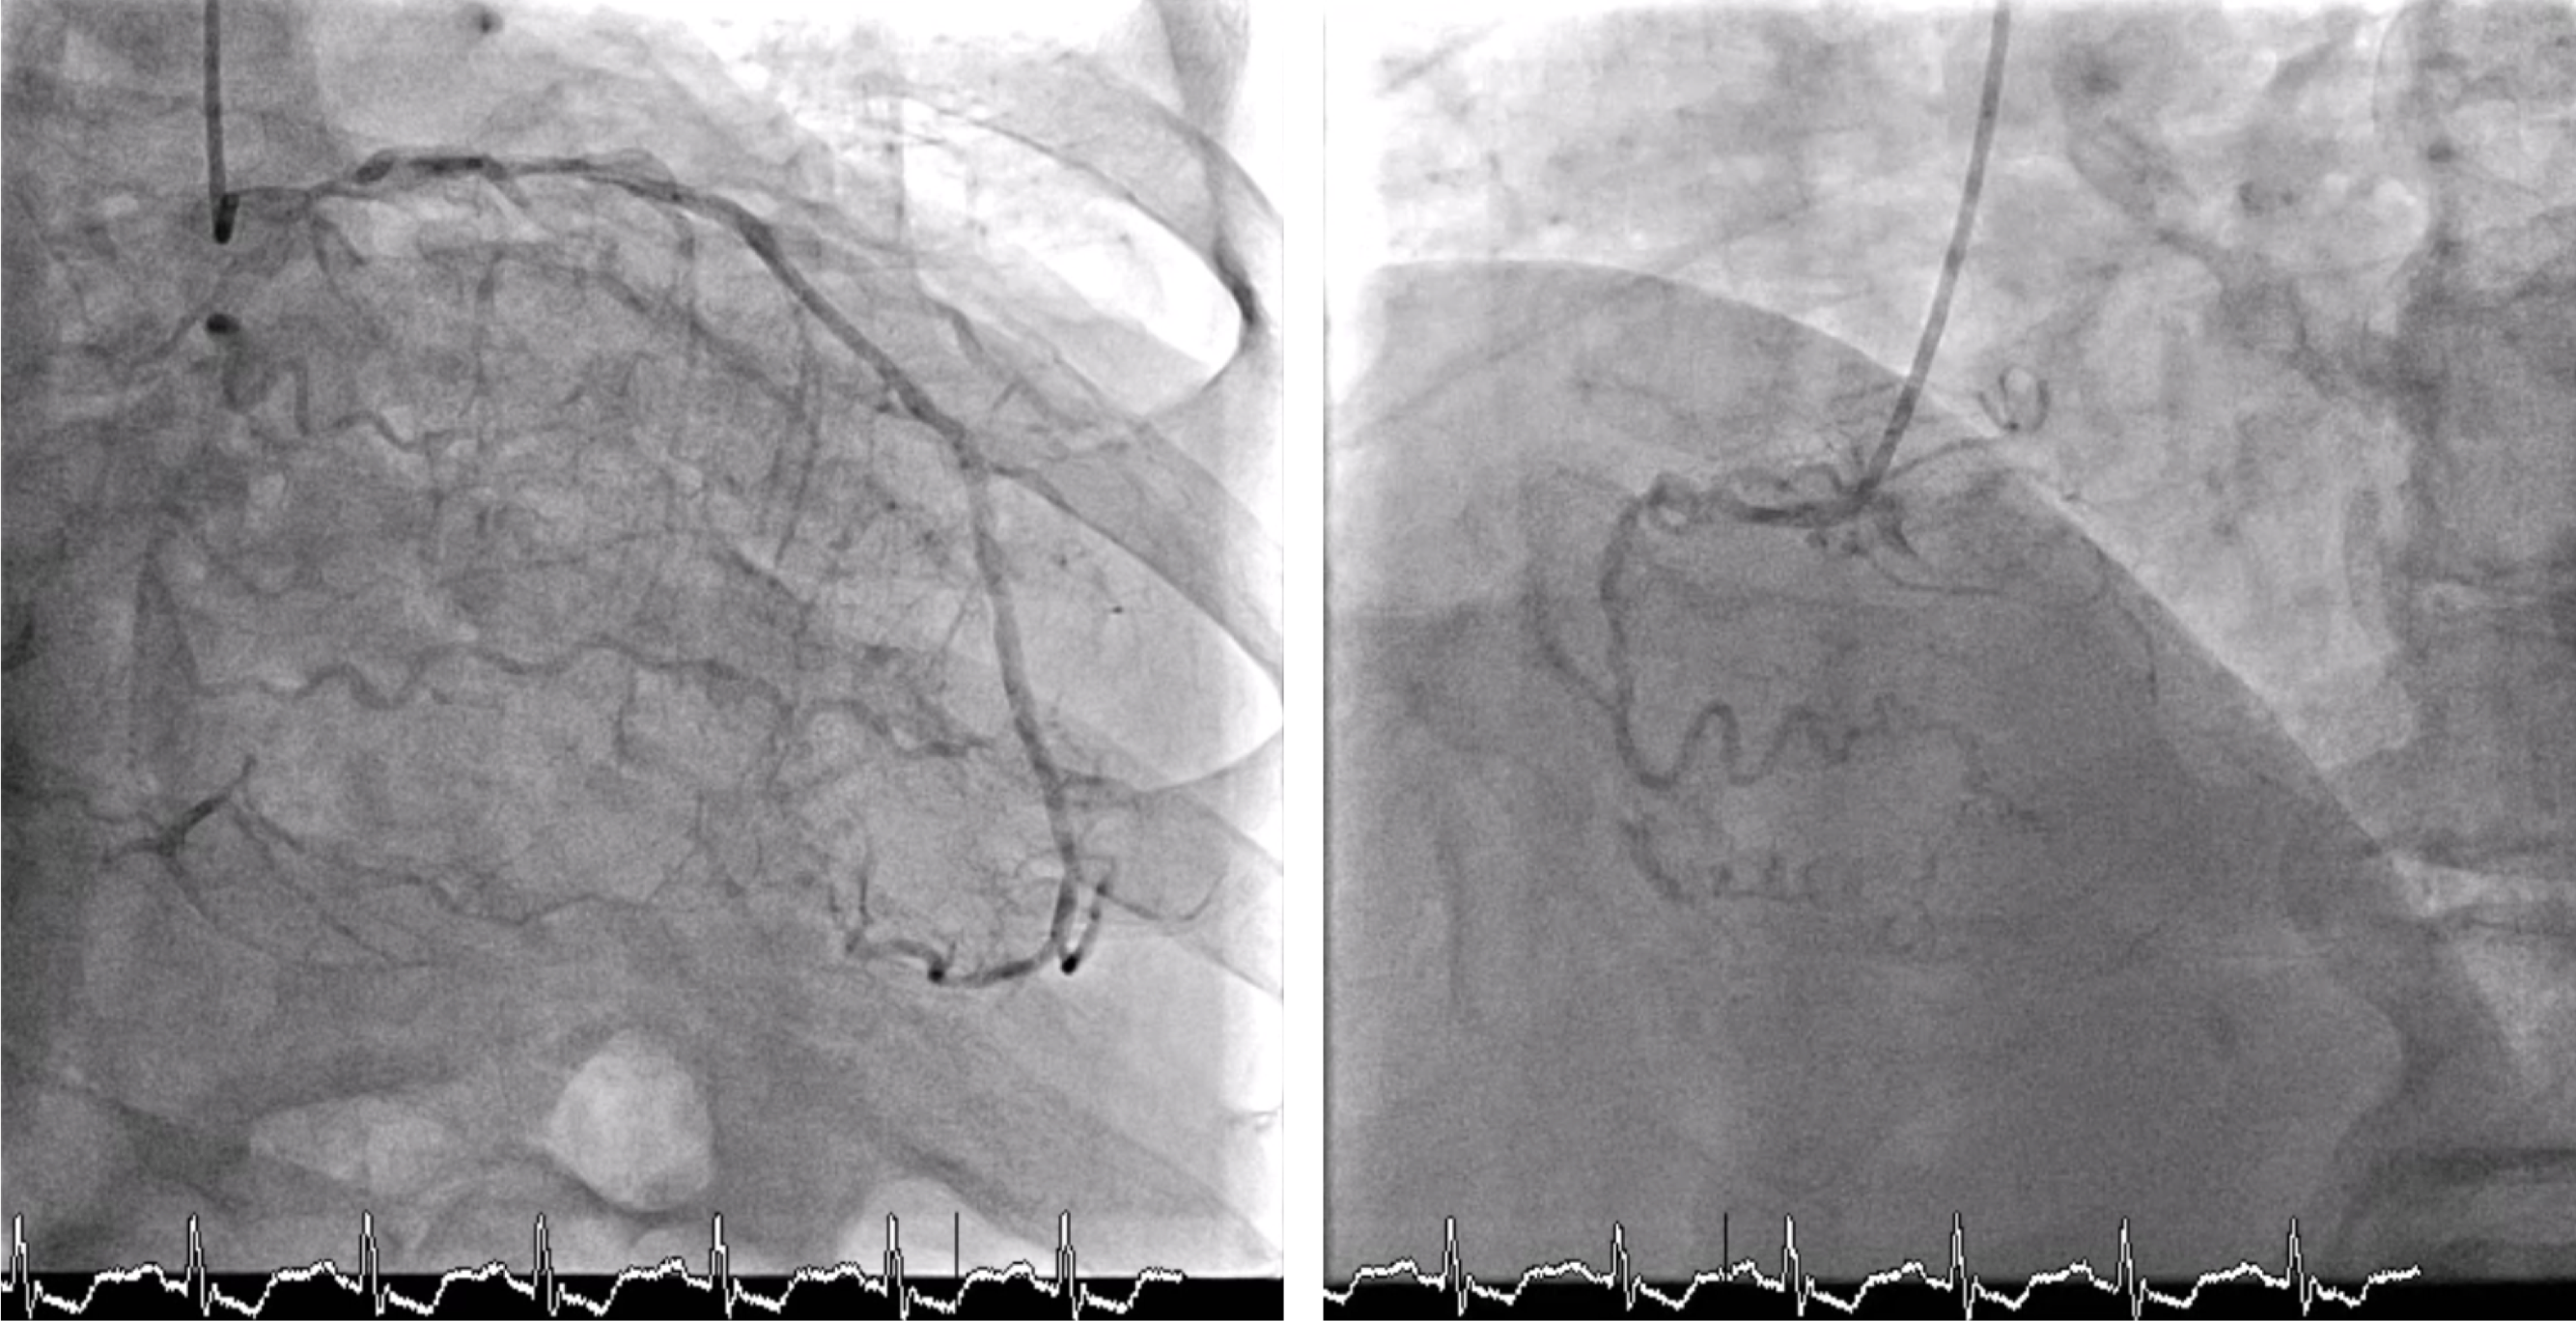

Procedural Step

Vascular duplex was performed instead of CT for large-bore access evaluation due to acute kidney injury, revealing severe stenosis of the left common femoral artery. Despite this, an Impella CP¢ç sheath was successfully inserted using contralateral injection and fluoroscopic-guided puncture, and the device was advanced into the left ventricle uneventfully. Initial hemodynamic data from the pulmonary artery catheter showed elevated pulmonary artery wedge pressure (32 mmHg), pulmonary hypertension (68/22 mmHg, mean 43 mmHg), and a low cardiac index (1.98 L/min/m©÷) without vasopressors or inotropes. The wedge pressure decreased to 23 mmHg after Impella insertion, demonstrating effective hemodynamic support. A Medtronic 8 Fr EBU 3.5 guiding catheter with a side hole was used to engage the left coronary artery. IVUS of the LAD and LCx showed diffuse mixed calcified and fibrotic plaques with similar luminal diameters from the ostium to the proximal segments. Based on these findings, an upfront two-stent Culotte strategy was adopted. Both ostial-to-proximal LAD and LCx were pre-dilated with 3.0 mm balloons, followed by successful deployment of 3.0 ¡¿ 23 mm and 3.0 ¡¿ 28 mm drug-eluting stents to the LCx and LAD, respectively. The proximal-to-mid LAD and diagonal branch were also treated. After stent implantation, the patient was weaned smoothly from Impella, with pulmonary artery wedge pressure mildly elevated (23 mmHg after insertion and 25 mmHg post-procedure).